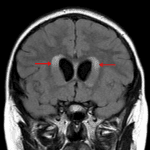

- Associated obstructive hydrocephalus and periventricular edema

- Associated effacement of the fourth ventricle and obstructive hydrocephalus with periventricular edema